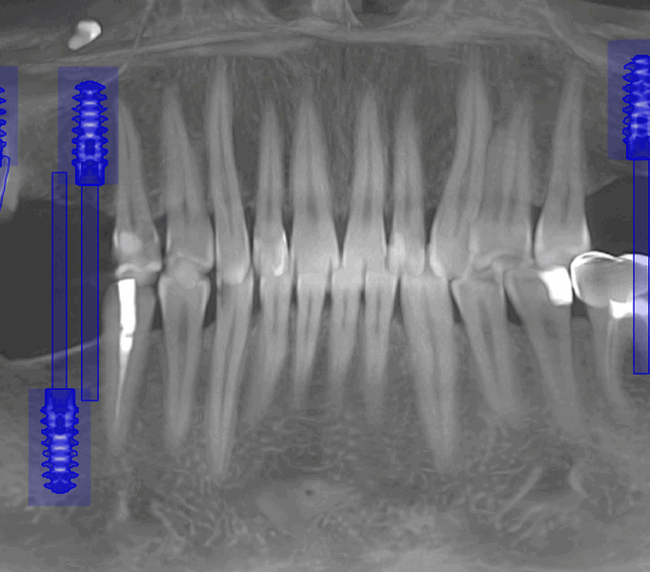

- Consultația inițială și planificarea tratamentului (inclusiv tomografie CBCT)

- Inserarea implanturilor dentare (chirurgie ghidată digital)

- Tehnologie digitală de ultimă generație – scanare 3D, design asistat digital

- Chirurgie implantologică ghidată, minim invazivă